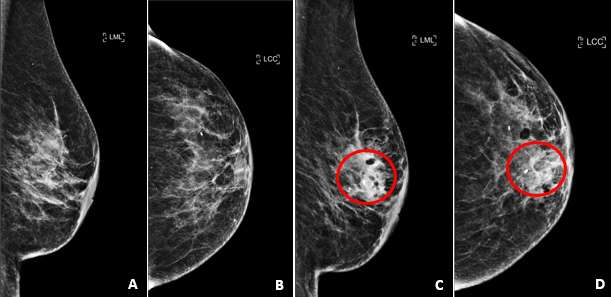

Figure 1: Greyscale (A) and color (B) ultrasound images demonstrate a well-defined hypoechoic fluid collection with posterior acoustic enhancement and without internal vascularity. In this patient with a recent history of breast surgery, findings are favored to represent a seroma.

On ultrasound, seromas will present as a fluid-filled collection, which is well-circumscribed and anechoic or hypoechoic in echogenicity. The fluid within the seroma may be simple in appearance or mildly complex, often exhibiting posterior acoustic enhancement. When direct pressure is applied with the ultrasound probe during imaging, the seroma may compress, causing a change in shape or size.